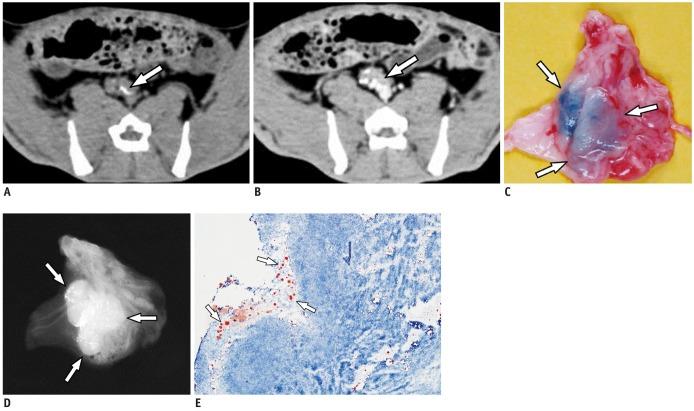

CT 淋巴造影术经碘化油示踪检测兔大腿VX2 癌前哨淋巴结。

Sentinel node mapping of VX2 carcinoma in rabbit thigh with CT lymphography using ethiodized oil.

To assess the feasibility of computed tomography (CT) lymphography using ethiodized oil for sentinel node mapping in experimentally induced VX2 carcinoma in the rabbit thigh.

This experiment received approval from the institutional animal use and care administrative advisory committee. Twenty-three rabbits with VX2 carcinoma in the thigh underwent CT before and after (1 hour, 2 hour) peritumoral injection of 2 mL ethiodized oil. After the CT examination, sentinel nodes were identified by peritumoral injection of methylene blue and subsequently removed. The retrieved sentinel and non-sentinel lymph nodes were investigated with radiographic and pathologic examinations. Based on the comparison of CT findings with those of radiographic and pathologic examinations, the diagnostic performance of CT for sentinel node identification was assessed.

RESULTS

All 23 rabbits showed 53 ethiodized oil retention nodes on post-injection CT and specimen radiography, and 52 methylene blue-stained nodes at the right femoroiliac area. Of the 52 blue-stained sentinel nodes, 50 nodes demonstrated ethiodized oil retention. Thus, the sentinel node detection rate of CT was 96% (50 of 52). On pathologic examination, 28 sentinel nodes in 17 rabbits (nodes/rabbit, mean ± standard deviation, 1.7 ± 0.6) harbored metastasis. Twenty seven of the 28 metastatic sentinel nodes were found to have ethiodized oil retention.

CONCLUSION

评估使用碘油计算机断层扫描(CT)淋巴造影术对兔大腿VX2 癌实验诱导的前哨淋巴结定位的可行性。

材料和方法

本实验获得机构动物使用和护理行政咨询委员会的批准。23 只大腿患有 VX2 癌的兔子在瘤周注射 2 毫升碘油前后进行 CT 检查。CT 检查后,通过瘤周注射亚甲蓝识别前哨淋巴结,然后切除。对取回的前哨和非前哨淋巴结进行放射学和病理学检查。基于 CT 发现与放射学和病理学检查的比较,评估 CT 对前哨淋巴结识别的诊断性能。

结果

所有 23 只兔子在注射后 CT 和标本放射摄影上均显示 53 个碘油保留淋巴结,在右股髂区显示 52 个亚甲蓝染色淋巴结。在 52 个蓝色染色的前哨淋巴结中,有 50 个节点显示碘油保留。因此,CT 对前哨淋巴结的检测率为 96%(50 个中的 52 个)。在病理检查中,17 只兔子的 28 个前哨淋巴结(每个兔子的淋巴结/兔子,平均值±标准差,1.7±0.6)有转移。28 个转移性前哨淋巴结中有 27 个发现有碘油保留。

结论

使用碘油的计算机断层扫描淋巴造影术可能适用于兔大腿实验诱导的 VX2 癌前哨淋巴结定位。